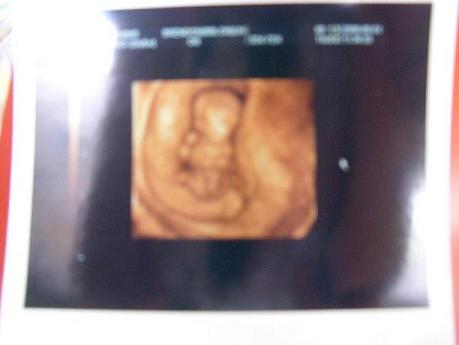

Kép Babuci 11 het es 6 nap

na masodszorra sikerult :D

azt mondtak, hogy minden oke. mozgott egy kicsit, de nem sokat. mondogatta a pasi, hogy meg tul kicsi. a nyaki redo 1.7 volt. azt is csak azert merte meg a ficko, mert kertem.

a brendont nem ajanlanam senkinek, mert nem voltak valami kedvesek, es hamar kidobtak minket. 10perc volt az egesz, 9 ezer forimt volt. vittunk egy vhs kazettat, arra felvettek a "musort" meg kaptunk egy darab kepet. azt hiszem megfogadom baratnom tanacsat es legkozelebb a 4dgenesisbe megyunk.

en tegnap voltam 4d-n 11hetesen es 6 naposan, es megmertek.